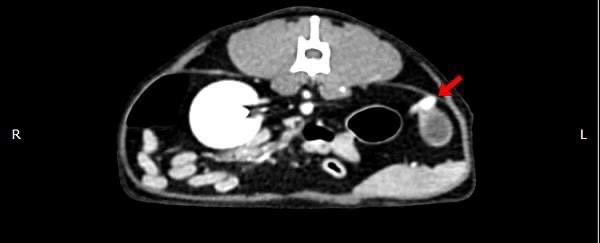

卵巢殘留

卵巢殘留是指雌性動物在進行絕育手術後,仍然有部分卵巢組織殘留,進而導致術後仍然反覆發情,並可能繼發子宮殘端蓄膿、乳腺腫瘤等疾病。而殘存的卵巢,由於體積小且子宮角已被摘除,往往難以找尋。幸而隨著動物醫療進步,依靠電腦斷層、內視鏡等先進設備,卵巢殘留的情況已不再難以處理。

小花是一隻一歲多的母貓,半年前曾在其他醫院做過絕育手術,但手術當下卻只找到單側的子宮卵巢,且在這半年當中仍然反反覆覆地發情,讓飼主十分擔心,於是來到築心尋求治療。在了解小花的狀況後,我們為小花安排了電腦斷層掃描,並在腹腔的左側發現了疑似殘存的卵巢影像(見圖示),接著,在影像定位的協助下順利開腹取出殘存的卵巢和發育異常子宮角,而在殘存的子宮內已然形成了子宮蓄膿。

幸虧子宮蓄膿的情形尚不嚴重,並沒有造成感染範圍的擴散,手術後經過一小段時間的修養,小花目前已經順利拆線,在家過著無憂無慮的生活囉。